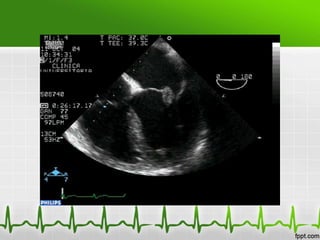

Endocarditis infecciosa

Ecocardiograma

•   Sensibilidad (60-70%) para vegetaciones

•   Aumenta con ETE

•   No detecta vegetaciones <2mm

•   Un estudio negativo no excluye

•   Util para indicar Tto. Quirurgico

•   Diagnóstico de complicaciones

Ecocardiografía

 Ecocardiograma Transtoracico (ETT)

-Sensibilidad 46% y especificidad de 95%

– Primera linea en sospecha de EI.

– Mayor rendimiento en valvulas nativas

– ETT no descarta EI.

• Ecocardiograma Transesofágico (ETE)

-Sensibilidad del 93% y especificidad del 96%

– Mayor sensibilidad

– Indicado v. protesicas

– Complicaciones cardiacas

– Dudoso ETT

– Bacteremias por Hongos o S. aureus